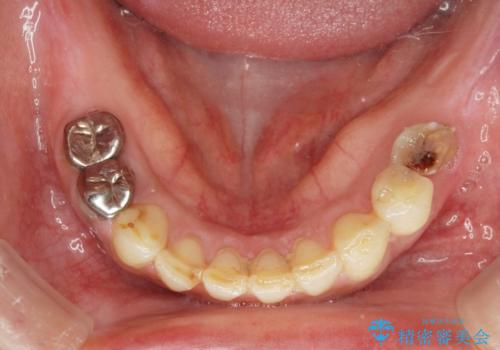

痛くて噛めない インプラントで全て治療したい

- 痛くて噛めない、これまでだましだまし治療をしてきたがこれを機にすべてきっちりと治したい、口の中の悩みを解決したいと来院されました。

抜歯や歯周病治療、欠損補綴を含め、全顎的な治療を計画・提案します。

口腔内に歯の破折や歯周病、虫歯、欠損など複数の問題が存在する場合局所的に問題を解決していくのではなく全顎的な治療を行っていくことで長期的な予後を見込むことができます。